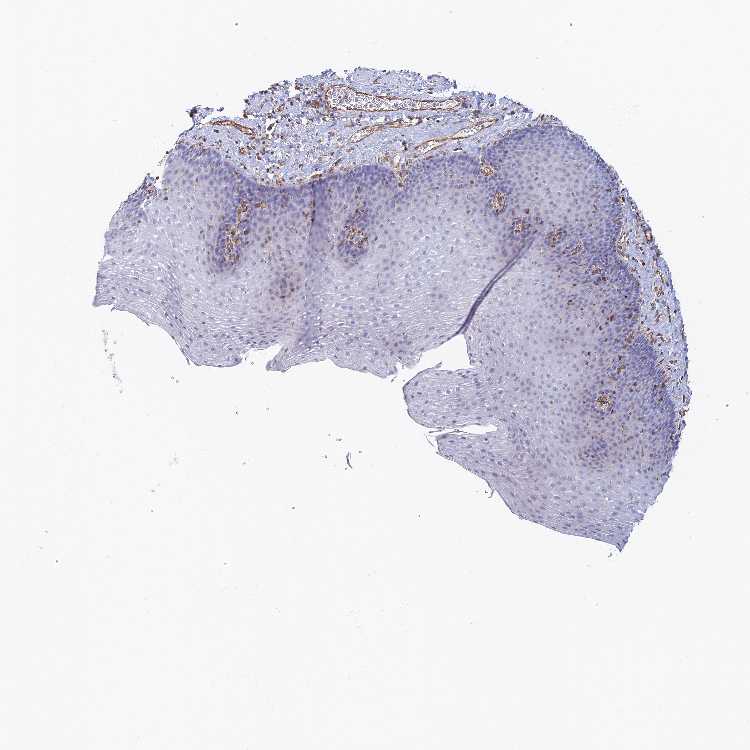

ESOPHAGUS - Antibody stainingi

Antibody staining in the annotated cell types in the current human tissue is reported as not detected, low, medium, or high, based on conventional immunohistochemistry profiling in selected tissues. This score is based on the combination of the staining intensity and fraction of stained cells.

Each image is clickable and will lead to virtual microscopy that enables deeper exploration of all samples and also displays staining intensity scores, fraction scores and subcellular localization as well as patient and tissue information for each sample.

Antibody HPA043589

Squamous epithelial cells Not detected